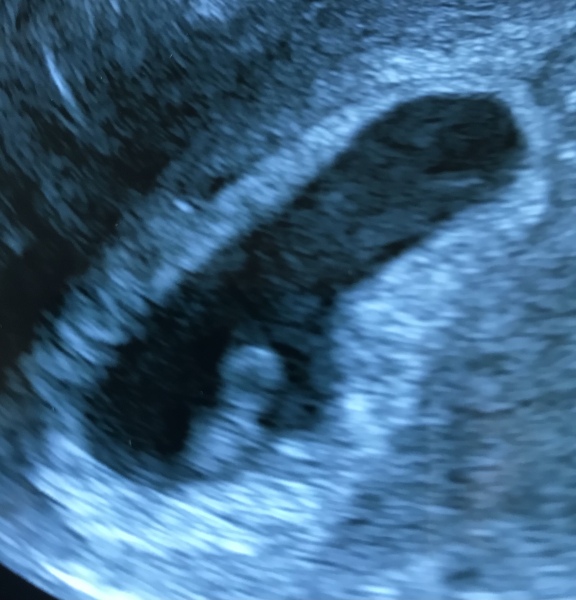

Just back from my scan, and after a little bit of a scare cos they couldn’t see anything at first and they asked me to go for a walk for 10 mins, little bean made an appearance! Measuring dead on 6 weeks 4 days which is exactly what I am based on ovulation and we saw a little heartbeat 🥹💕

@thelma57 Oh that's such a good scan photo, looks like it's looking right at you 🥰

@thelma57 such good news. Cant imagine how you felt when they couldnt find the little one. Lovely scan pic too!